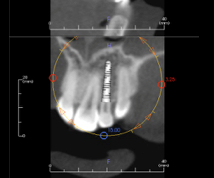

Implant mapping is a concept that creates ideal separation between dental implants and teeth. In today’s digital world, “mapping” is performed by computer programs, such as “Simplant” or “Anamage.”

Through these software programs, implant placement is directed and planned based on the detailed information provided by the cone beam X-ray. The implants may be “digitally” placed with high accuracy. Surgeons are very reliant on these software tools.

From our discussion above, the restorative dentist needs to understand and apply the mapping concepts in fabricating surgical guides and mapping the implant on the model, which aids the restorative dentist in creating an accurate “pilot hole” in the surgical guide provided to the surgeon.

Implant position is critical, depending upon whether the implant restoration will be cement or screw retained. The restorative dentist must determine this retention information and forward it to the implant surgeon prior to placement. Mapping is the key to analyzing the implant position precisely.

An important dimension is the distance between an implant platform and an adjacent tooth. If the platform is placed too close to the tooth, the blood supply to the bone and root may be compromised.

Additionally, the gingival tissue contours may be altered. Bone loss and altered papillae are likely sequelae. The common implant/tooth distance should be no less than 1.5 mm.

The distance between two dental implants is crucial to establishing a healthy biological dimension. If there is less than 3.0 mm between two implants, the interproximal bone will flatten, and papilla formation is not likely to occur. Normal bone healing and remodeling create a detrimental “crossover” effect with implants too close to one another, and progressive bone loss may occur.

Facial/lingual implant positioning is just as critical. Placing an implant less than 3.0 mm from the facial tissue will likely result in gingival recession and facial bone loss. An implant placed too palatal will create an emergence profile “overhang” and result in dental hygiene limitations and difficulty. Mapping the implant placement on a stone cast will provide a “visual reference” of predictability for both the restorative dentist and the surgeon.